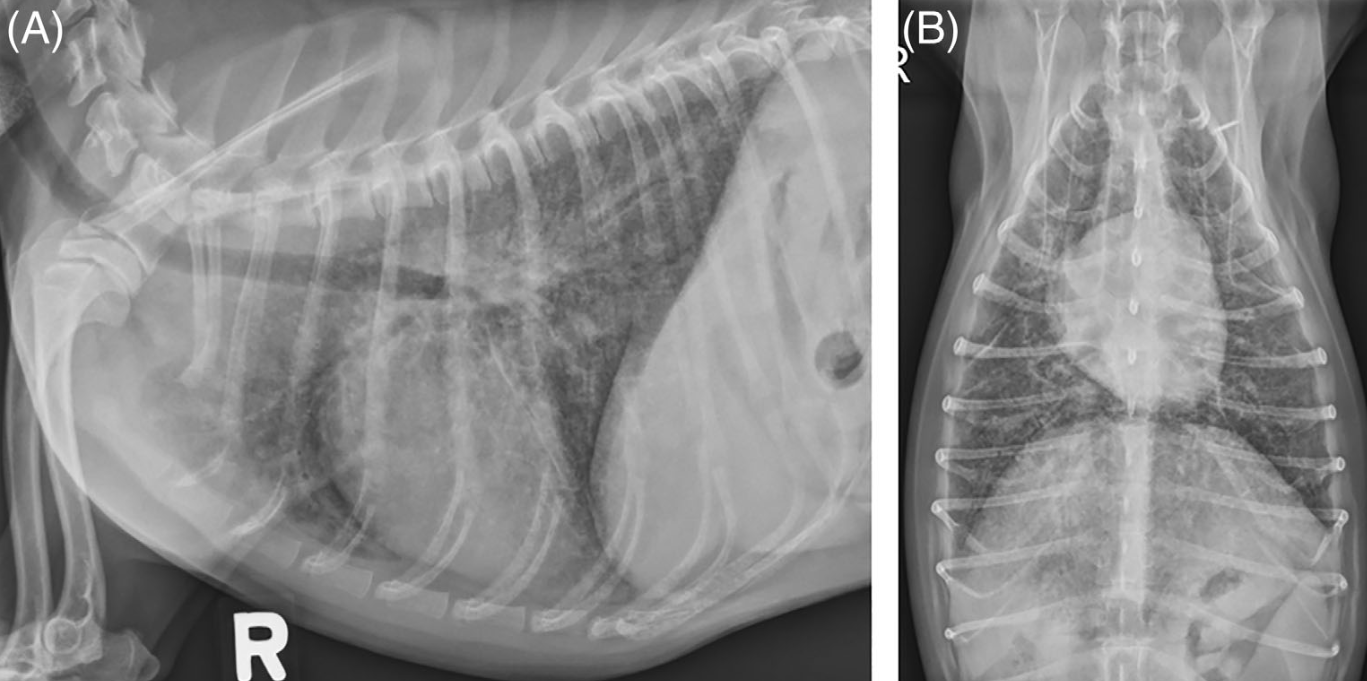

역시 주증은 폐포감염에 의한 폐섬유화증이 문제이다.

뚜렷한 간질 침윤때문에 간질성 폐렴이나 기관지염으로 치부될 수 있으나 특징적으로 다른 원인 없이 호흡이 가파른 양상을 보일 수 있는게 특징,

본인이 겪은 증례에서는 폐포가 결국 섬유화로 뻣뻣해져서 찢어져서 기흉으로 급사한 사례도 있었으니 실제 호흡이 빠른것은 매우 좋지 않은 상태로 보아야 한다.